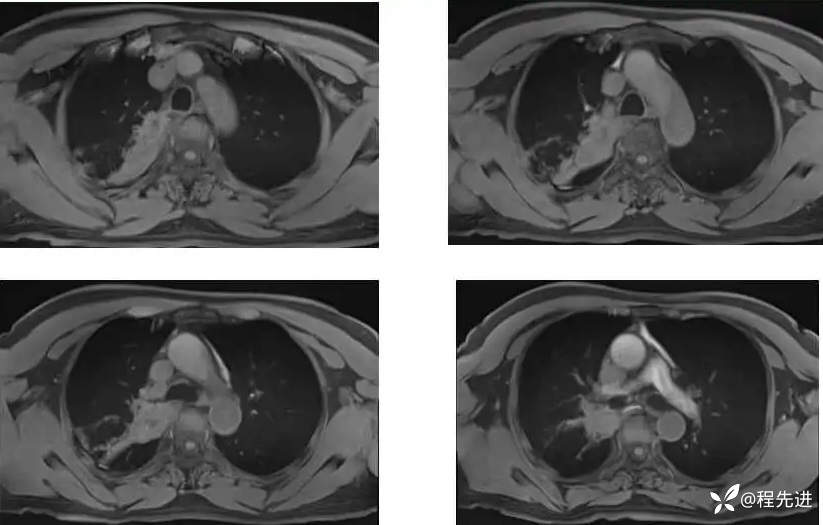

T2;

T1压脂: